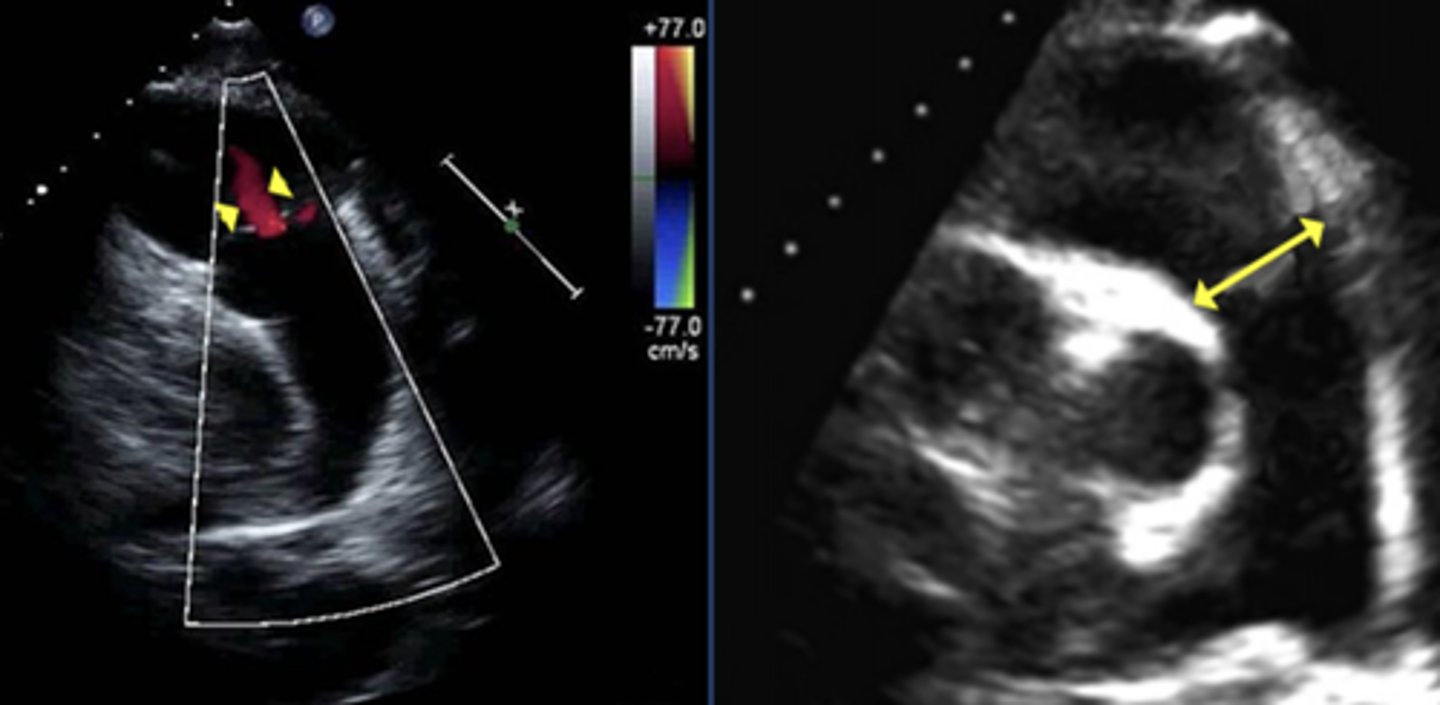

2D Features of Chronic PR

RV dilation with normal function - overload

Flow Reversal in Pulmonary Artery Branches

Indicates severe PR